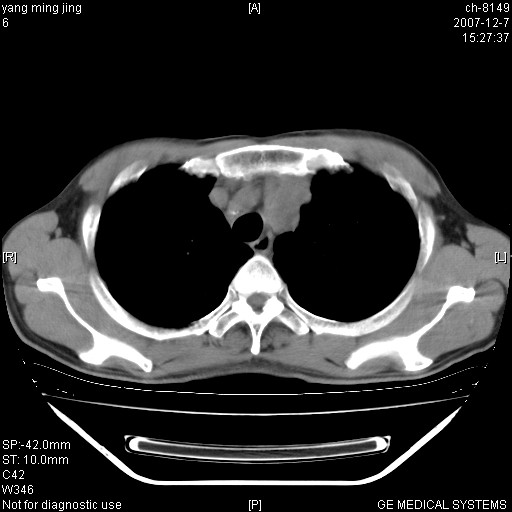

以下是引用zsl6918在2007-12-7 22:22:00的发言:[br]左肺上叶中心性肺癌并肺内及纵隔淋巴结转移,肝内转移。小细胞肺癌可能性大。

以下是引用狙击手在2007-12-8 11:03:00的发言:[br]考虑:左肺上叶中心性肺癌并肺内及纵隔淋巴结转移,肝内转移。